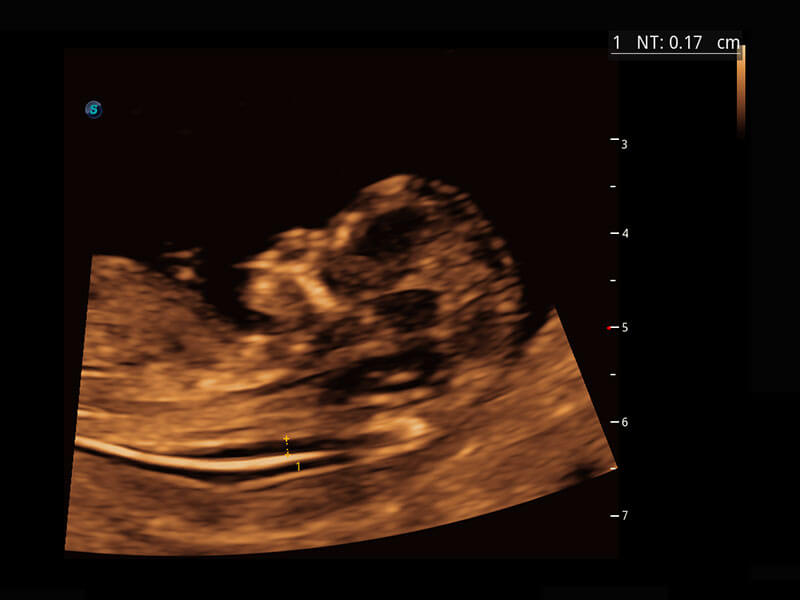

P60在胎儿早孕期超声筛查中为您带来优异的图像质量。

早孕-胎心

高分辨率容积成像-早孕胎儿

胎儿体循环

光影成像-孕囊